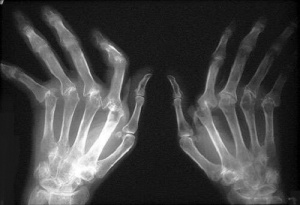

Başlıca ve gözle en kolay görünen belirtisi, eklemlerin şişmesi veya iltihaplanmasıdır. Bu durum şiddetli bir ağrıya neden olur. Romatoid artritte en sık etkilenen bölgeler bilekler, dirsekler, omuzlar, parmaklar, ayak parmakları, bel, ayak bilekleri ve dizlerdir.

Bu hastalıktan muzdarip kişiler, özellikle sabahları kalktıklarında eklemlerinde bir katılık hissederler. Bu kişilerde Romatoid nodülleri de belirebilir. Bunlar ciltteki (özellikle de ellerin ve ayakların arkasında) çıkıntılardır. Hastalığın ileri aşamalarında iltihaplanma yerini eklemlerin deformasyonuna bırakır.